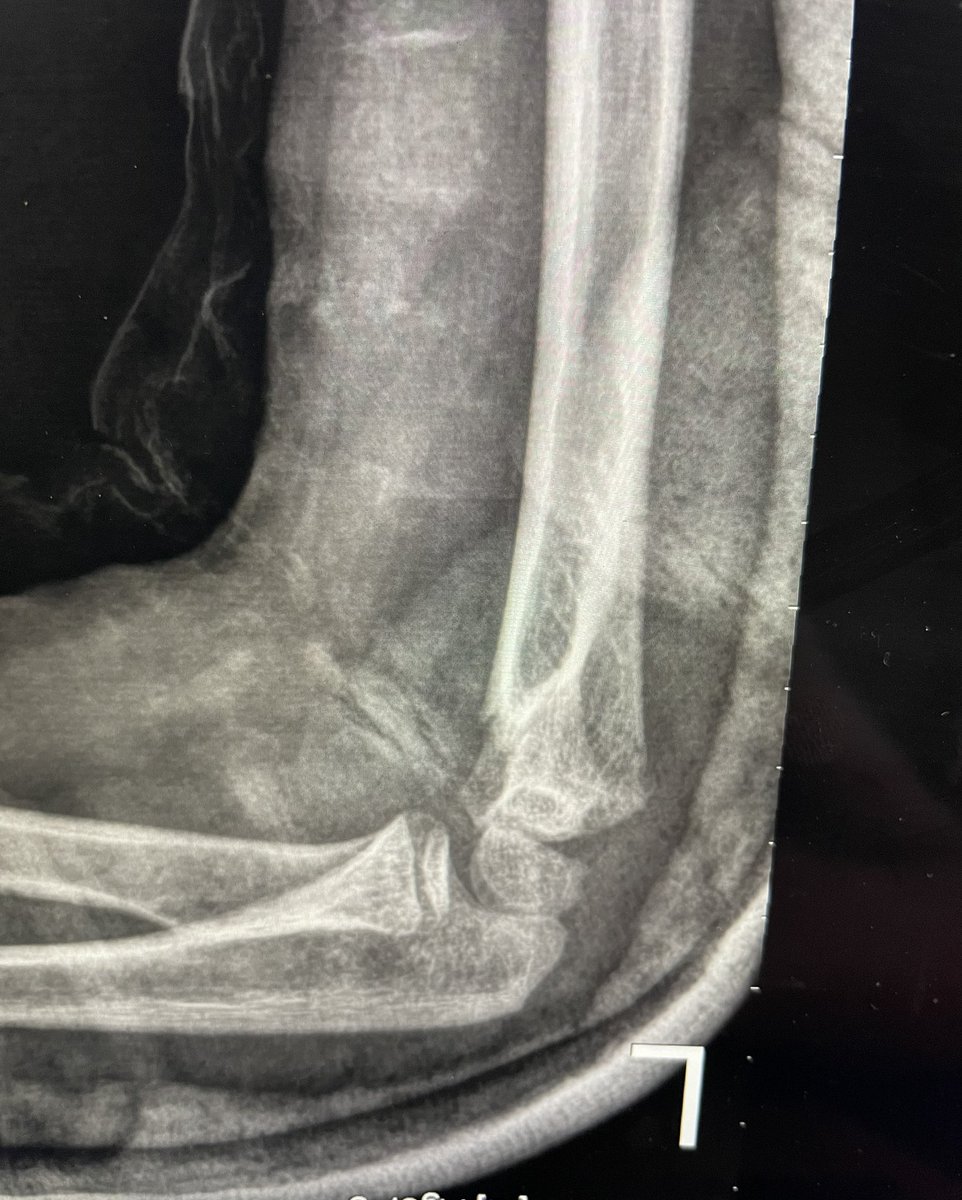

58 male fall from height last week !

Hx: HTN , CAD

Medicine :Aspirin 81 , Clopidogrel

When I aspirate hematoma there was about 6 ml blood

this is the pre_after reduction and the follow up today

He is not elderly in shape and body he looks like 40 !

1/2

@#orthotwitter